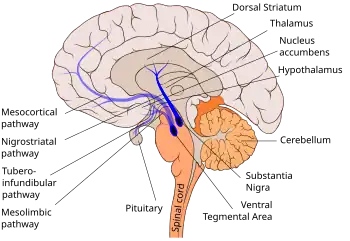

The nigrostriatal pathway is shown here in solid blue, connecting the substantia nigra with the dorsal striatum. | |

The nigrostriatal pathway is a bilateral dopaminergic pathway in the brain that connects the substantia nigra pars compacta (SNc) in the midbrain with the dorsal striatum (i.e., the caudate nucleus and putamen) in the forebrain. It is one of the four major dopamine pathways in the brain, and is critical in the production of movement as part of a system called the basal ganglia motor loop. Dopaminergic neurons of this pathway release dopamine from axon terminals that synapse onto GABAergic medium spiny neurons (MSNs), also known as spiny projection neurons (SPNs),[1][2] located in the striatum.

The substantia nigra is located in the ventral midbrain of each hemisphere. It has two distinct parts, the pars compacta (SNc) and the pars reticulata (SNr). The pars compacta contains dopaminergic neurons from the A9 cell group that forms the nigrostriatal pathway that, by supplying dopamine to the striatum, relays information to the basal ganglia. In contrast, the pars reticulata contains mostly GABAergic neurons.

The SNc is composed of a thin band of cells that overlies the SNr and is situated laterally to the A10 group of dopaminergic neurons in the ventral tegmental area (VTA) that forms the mesolimbic dopamine pathway. The SNc is easily visualized in human brain sections because the dopamine neurons contain a black pigment called neuromelanin which is known to accumulate with age.[4] The dopaminergic cell bodies in the SNc are densely packed with approximately 200,000 to 420,000 dopamine cells in human SNc and 8,000 to 12,000 dopamine cells in mouse SNc.[5] These dopamine cell bodies are localized to one of two chemically defined layers.[6] Those in the upper layer (or dorsal tier) contain a binding protein called calbindin-D28K which can buffer calcium levels inside the cell when it becomes too high or toxic. Dopamine cells in the lower layer (or ventral tier) lack this protein and are more vulnerable to the effects of neurotoxins (e.g. MPTP) that can cause Parkinson disease-like symptoms.[7][8] The dorsal tier dopamine cells have dendrites that radiate horizontally across the pars compacta, whereas ventral tier dopamine cells have dendrites that extend ventrally into the pars reticulata.[6][9]